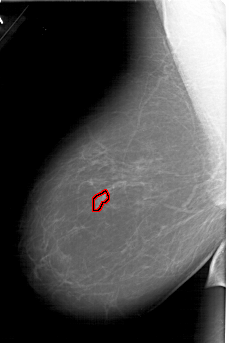

A_1644_1.LEFT_MLO

FILE: A_1644_1.LEFT_MLO.OVERLAY

TOTAL_ABNORMALITIES 1

ABNORMALITY 1

LESION_TYPE CALCIFICATION TYPE PLEOMORPHIC DISTRIBUTION CLUSTERED

ASSESSMENT 4

SUBTLETY 1

PATHOLOGY MALIGNANT

TOTAL_OUTLINES 1

BOUNDARY